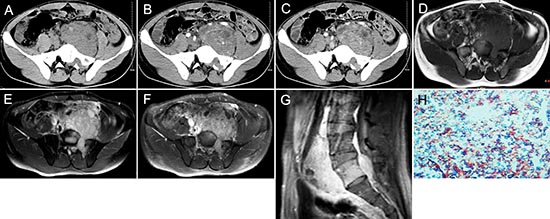

Figure 2: pPNET in a 21-year-old man. Precontrast CT images showed a lobular iso-dense mass with necrosis in the left retroperitoneum (A). Enhanced CT images showed the mass had heterogeneous contrast uptake (B-C). Precontrast MRI showed the mass had an ill-defined border that was iso-intense on T1WI (D) and hyper-intense on T2WI (E). Contrast MRI showed the mass had significant and heterogeneous enhancement (F). Sagittal enhanced MRI images showed the mass invaded the 5th lumbar vertebrae and spinal canal (G). The small round tumor cells were positive for CD-99 (H × 100).